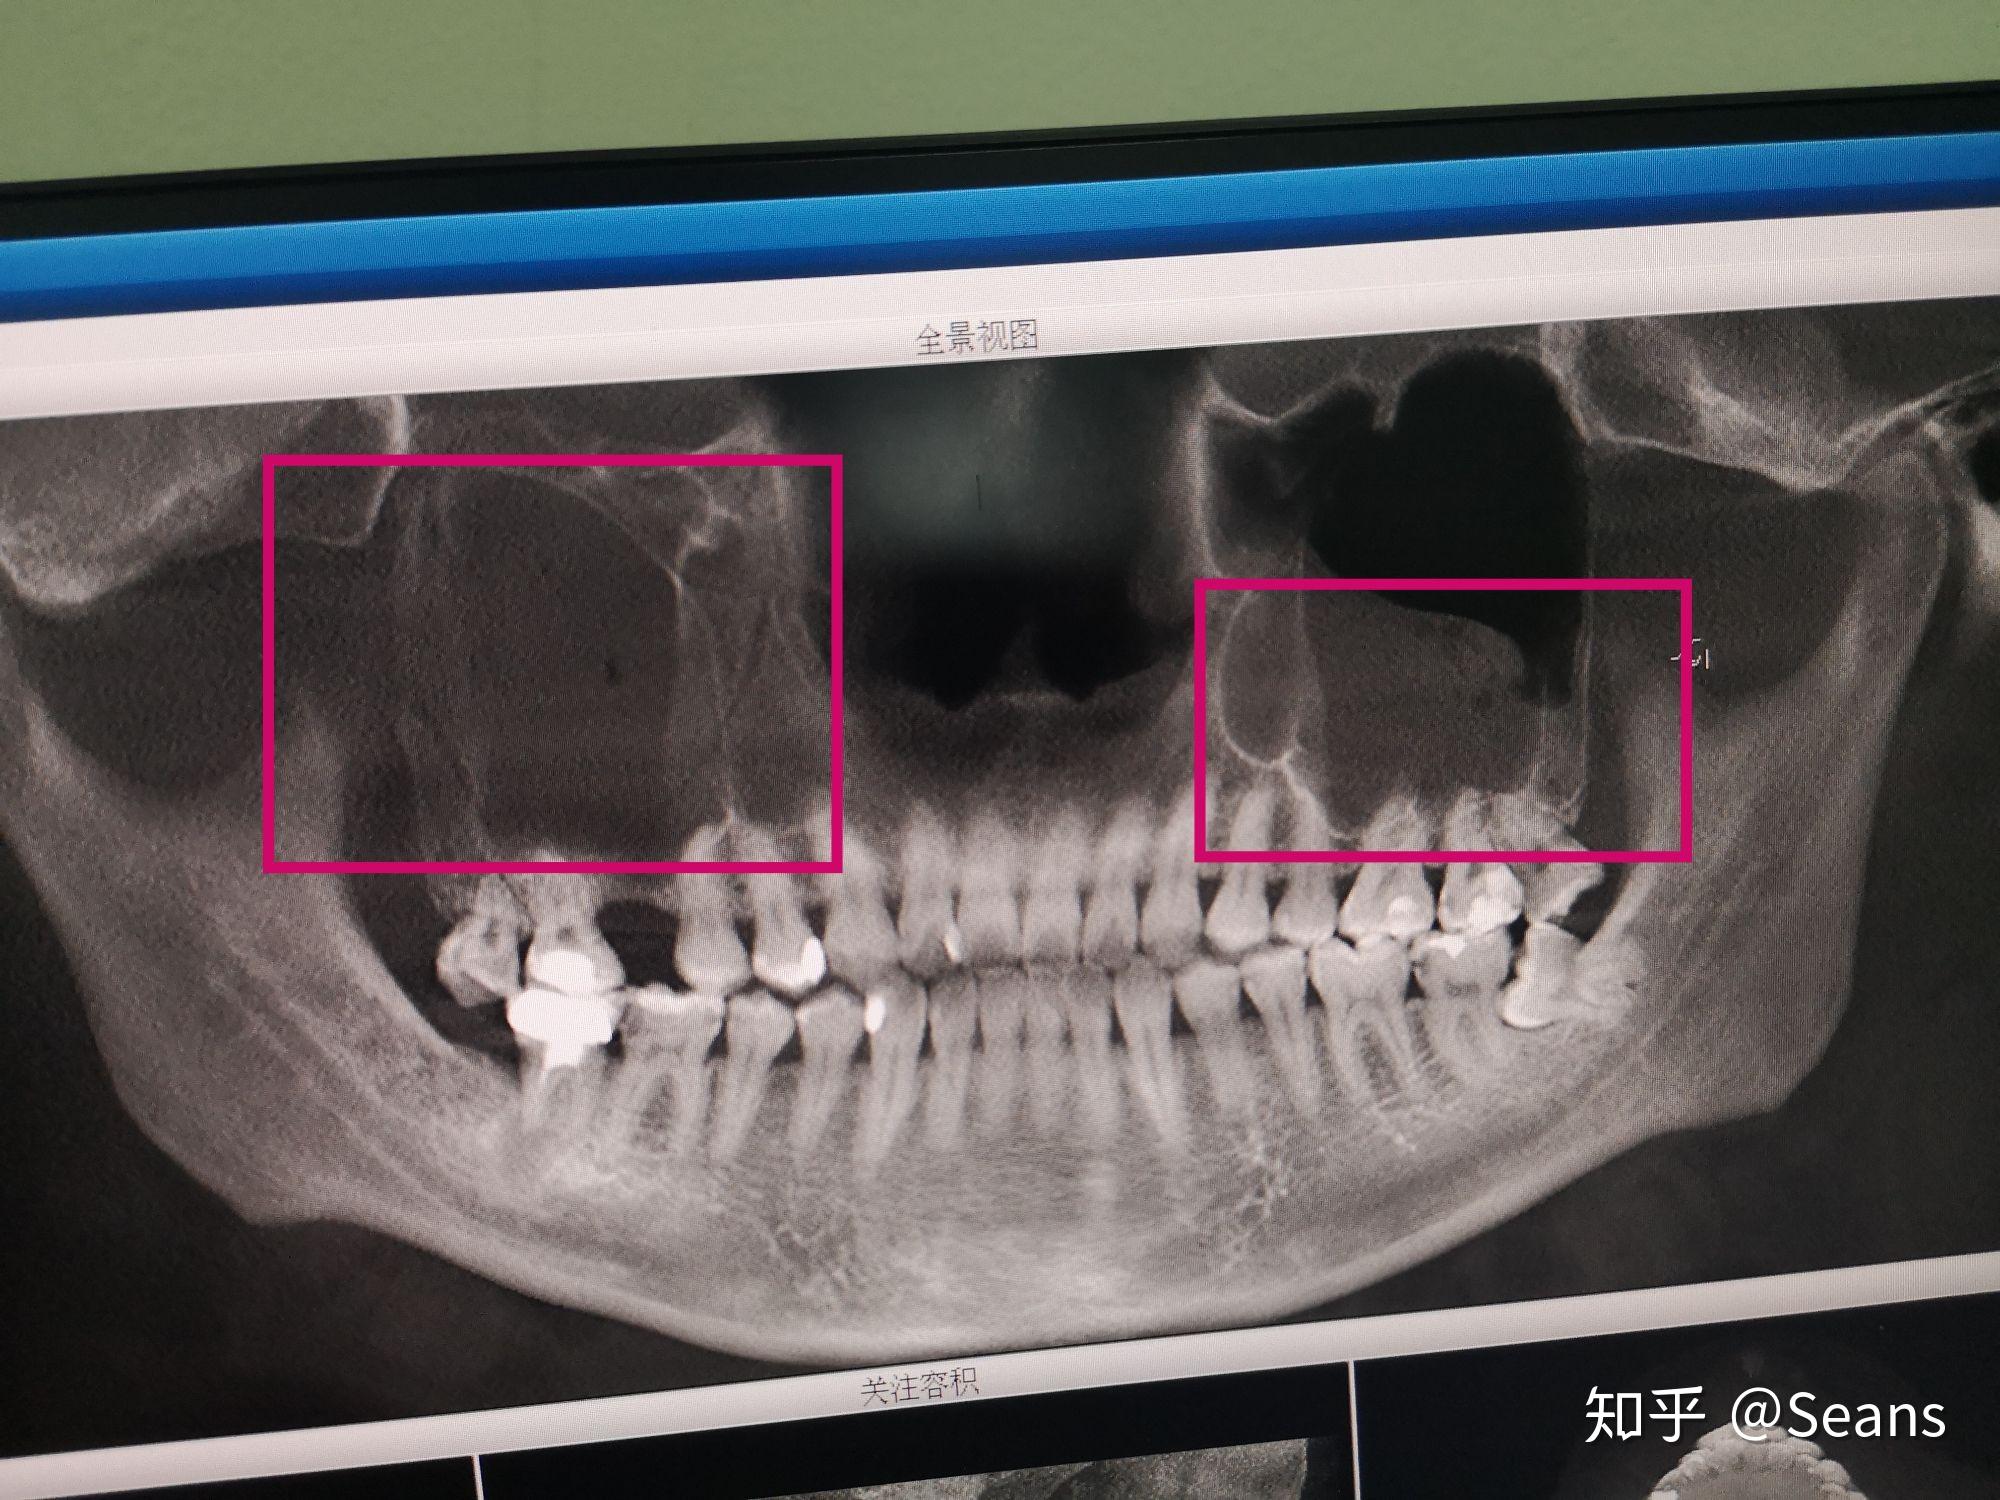

图13 负压吸引器吸出上颌窦腔内的牙根图14 口腔上颌窦瘘(cbct)图15

双侧上颌窦炎伴液体潴留是什么意思

图片尺寸1536x690